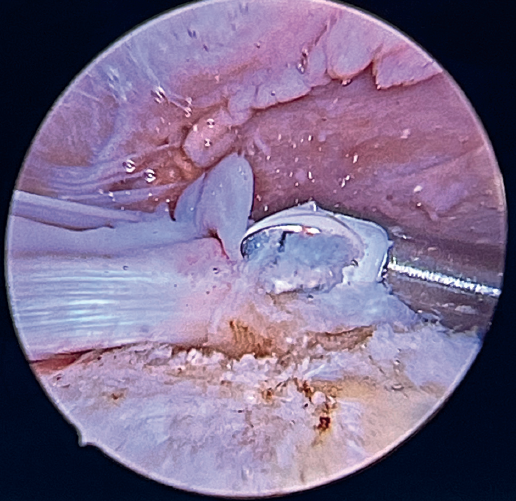

Tension-free repair of the supraspinatus tendon is then made, using the free thread left at the anchoring and taking advantage of the two sutures passed through and knotted to the proximal LPB fragment (Figures 8, 9 and 10).

The free suture remaining at the anchoring is passed through the anterolateral supraspinatus using a Scorpion® direct suture passer (Arthrex, Naples, FL, USA), as a sliding mattress suture over the implant.

One end of each of the sutures exiting the LPB is passed through the supraspinatus likewise using a Scorpion® direct suture passer (Arthrex, Naples, FL, USA). All the threads are left unknotted and are recovered through the anterior working portal so that they do not get in the way when working later on. Note that the two threads exiting the LPB and passing through the supraspinatus will not slide; it is therefore advisable to knot them and lower them later on with a knot pusher. This point allows repair of the anterior supraspinatus to be combined with fixation of the LPB in the anterolateral zone of the greater tuberosity.

Having passed both the anterior and the posterior sutures, we proceed to knot, through the lateral portal with a working cannula, each of the sutures, starting posterior and ending anterior.

Finally, the anterolateral supraspinatus threads are used in combination with the posterolateral tapes to establish a more lateral double row with two direct anchorings that allow the threads to be threaded through two loops(Biocomposite SwiveLock® C 4.75 × 19.1 mm, Arthrex, Naples, FL, USA). This achieves a tension-free double row repair of the supraspinatus, covering the superior capsular repair made with the LPB (Figure 11).